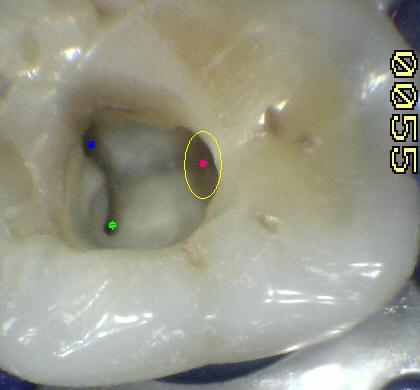

1º molar inferior (1,2,23,27)

En azul conducto mesio-vetibular

-

En verde conducto mesio-lingual

En rojo conducto distal

En amarillo un cuarto conducto,

si el conducto distal se encuentra desplazado hacia lingual,

existe una alta posibilidad de encontrar un cuarto conducto

|

Tres

conductos en piso de cámara pulpar, el conducto

distal se encuentra ensanchado en sentido

buco-lingual, debe sospechar la existencia de

dos conductos que comparten el orificio de entrada.

Cámara intraoral X10 aumentos. |